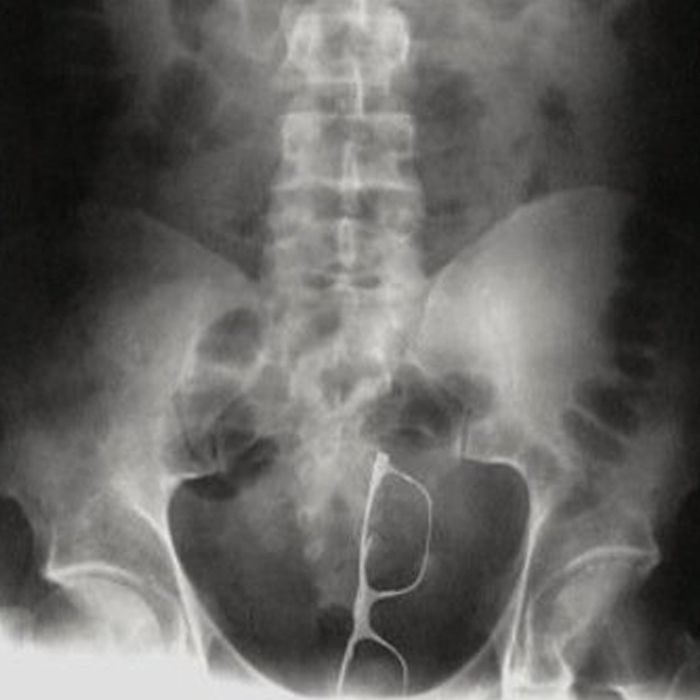

Sunglasses. I truly am at a loss on this one. A prank or dare maybe. BDSM punishment gone wrong?